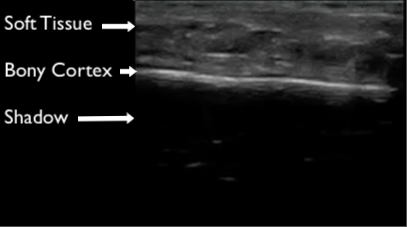

Figure 1 demonstrates normal appearing layers of soft tissue, fascia, muscle and bone. In general, the epidermis, fascia, and bone are hyperechoic compared to subcutaneous fat and muscle (which are hypoechoic). Bone will typically produce a clean shadow. Figure 2 demonstrates normal bony cortex in a long axis with shadow below. Muscle in a short axis is mostly hypoechoic with a few hyperechoic portions (Figure 3). In the long axis you can appreciate muscle fiber striations (Figure 4). Tendon in a long axis appears as a thin, well demarcated structure with striated fibers (Figure 5). Figure 6 demonstrates the principle of anisotropy, which is most apparent when imaging tendons and muscles. Muscle and tendon may appear focally hypoechoic depending on the angle of the transducer, but this is artefactual and will disappear with further interrogation. Figure 7 demonstrates a normal shoulder joint with no anechoic effusion and normal articulation of the glenoid and the humeral head.

Figure 2. Normal long axis bone appearance on ultrasound. The cortex appears hyperechoic with shadow deep to the cortex.